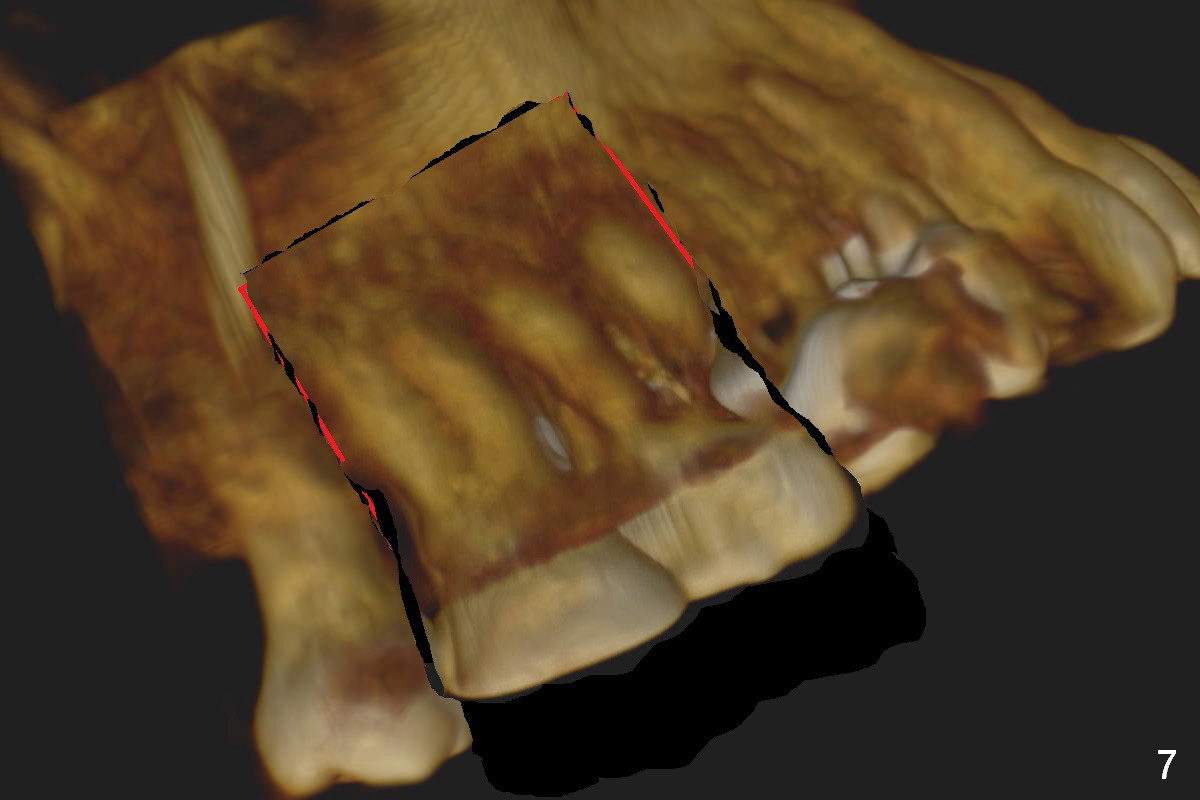

Orthodontic intrusion with mini-implants does not seem to work. When segmental brackets and bands are supplemented, the neighboring tooth (#14) becomes loose. CBCT 3 D and sagittal section show ~3 mm supraeruption of the teeth #2 and 3 (Fig.1,2). Diagnostic wax up demonstrates that the teeth #2 and 3 need to be intruded for 4 and 2 mm, respectively. Buccal gingival sulcus and anterior oblique incisions are shown in Fig.3 (red line). Osteotomy will be made with surgical fissure bur and chisels (Fig.4 red lines). The segment is down fractured (Fig.5 arrow). Apical bone is removed with acrylic bur and/surgical burs (Fig.6 cross lines). The segment is elevated and checked with a prefabricated splint out of diagnostic wax up. Insert a thicker orthodontic wire into brackets and bands buccally.